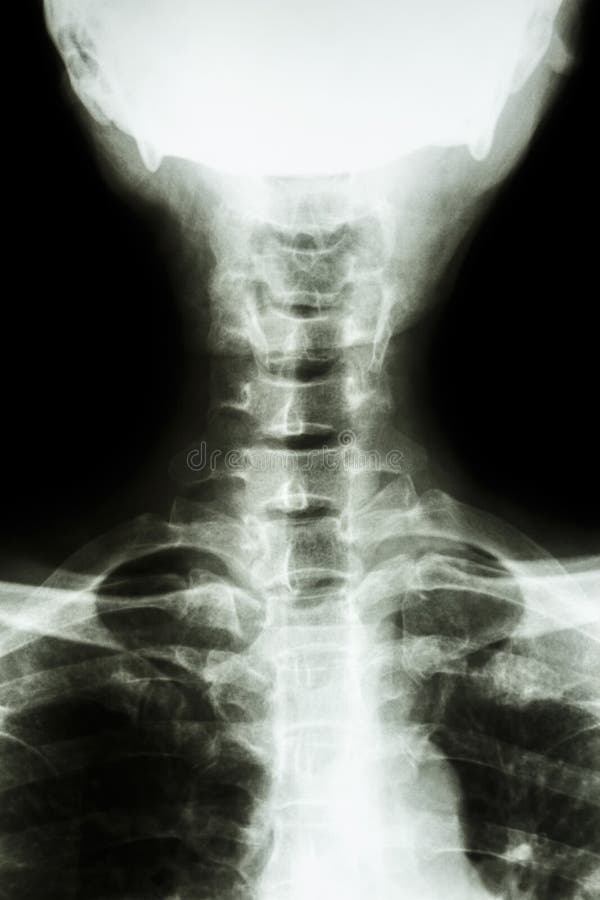

Рентген шеи белое пятно - фото презентация